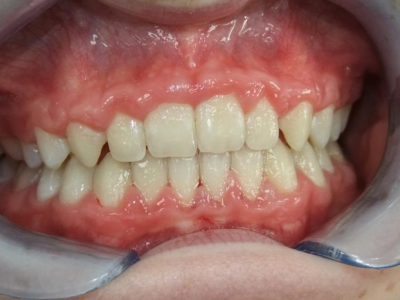

eindfoto

13-22 volledig vast onder- en bovenkaak + rotator

Retentie: wrap en c-c bar

Leeftijd bij retentie: 12 jaar